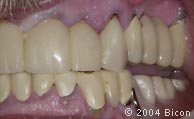

1. |

术前的微笑。 |